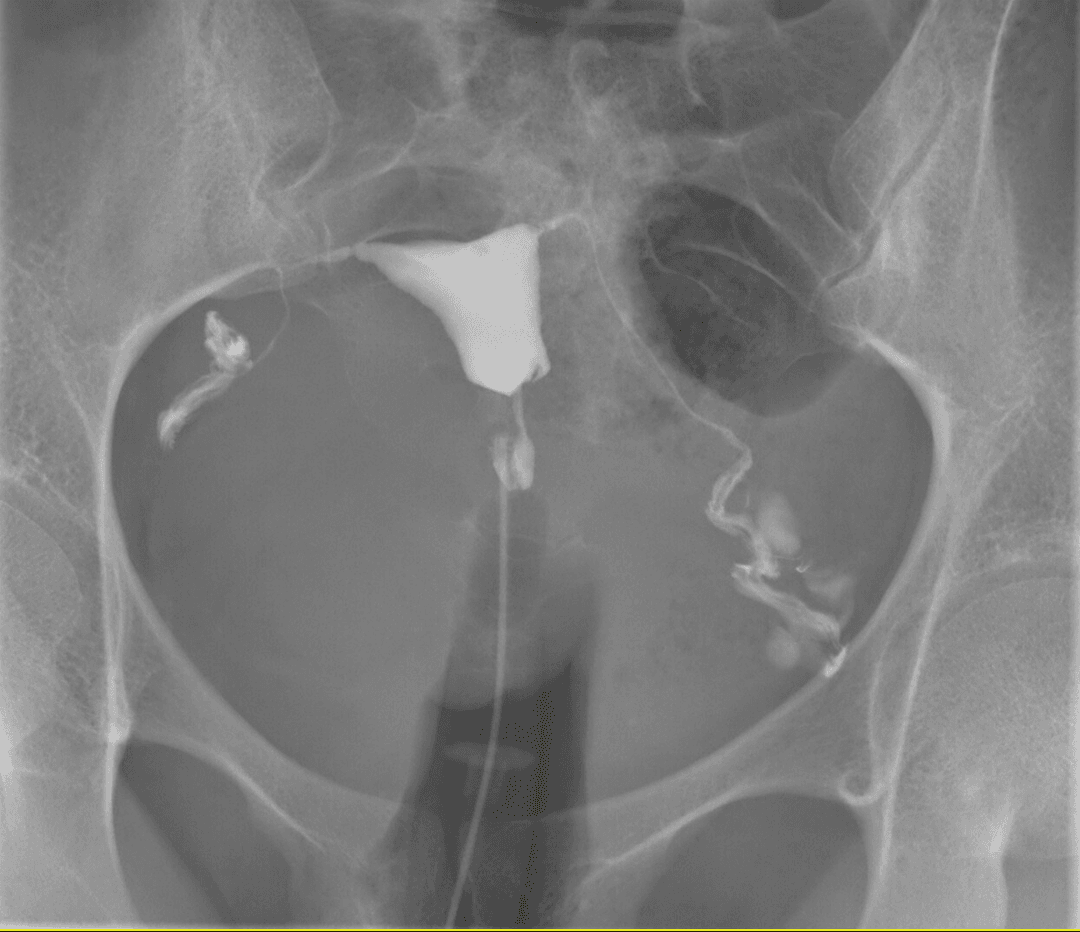

Hysterosalpingography (HSG), also known as uterosalpingography, is a radiologic procedure to investigate the shape of the uterine cavity and the shape and patency of the Fallopian tubes. It is a special x-ray procedure using dye to look at the womb (uterus) and Fallopian tubes. In this procedure a radio-opaque material is injected into the cervical canal, and radiographs are taken. A normal result shows the filling of the uterine cavity and the bilateral filling of the Fallopian tube with the injection material. To demonstrate tubal rupture, spillage of the material into the peritoneal cavity needs to be observed. Hysterosalpingography has vital role in treatment of infertility, especially in the case of fallopian tube blockage. HSG is considered a diagnostic procedure. It is used in the workup of infertile females to assess the patency of fallopian tubes, assess the competency of the cervix or congenital abnormality of the uterus in multiple miscarriages, assess the patency of fallopian tubes after surgery or tubal ligation, or before reversal of tubal ligation. Rarely, HSG is used to assess the integrity of a Caesarean scar. Occasionally, HSG may also have therapeutic benefits for infertility treatment. When oil-based contrast is used, rates of pregnancy increase by about 10% compared to water-based contrast. A meta-analysis revealed 3.6 times greater odds (OR = 3.6) of pregnancy with oil-based contrast compared to no hysterosalpingography. This effect is thought to be due to the flushing action of the contrast into the uterus that causes dislodgement of mucus plug, debris, or opening of mild adhesions in the fallopian tubes. HSG is contraindicated during menstruation, suspected cancer, pregnancy, unprotected sexual intercourse during the menstrual cycle, any purulent discharge from the vagina, or if the individual was diagnosed with pelvic inflammatory disease six months previously. For those with hypersensitivity to contrast, HSG is relatively contraindicated. Either high osmolar contrast material (HOCM) or low osmolar contrast material (LOCM) can be used.